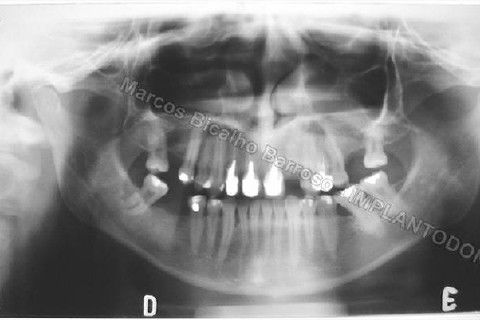

Este caso tem o objetivo de demonstração da técnica que normalmente sigo ; em casos onde ocorre fratura da raiz e consequentemente abscessos, com ou sem formação de fístula. Neste caso fiz a exodontia com preenchimento do alvéolo com biomaterial (osso bovino liofilizado + coágulo do paciente). Após 90 dias, mais ou menos, instalei o implante. Esperei mais 4 meses e realizei ontem (12/11/2010) a instalação do cicatrizador com o cuidado de preservar tecido mole, sem remoção de material, apenas afastando gengiva e "enrolando" a sobra de mucosa em direção a face vestibular, para promover conservação de papila futuramente. Se ocorrer excesso de papila, sem problema, remove-se um pouco, mas a intenção é não deixar faltar, o que resultaria em indicação para enxertos gengivais.